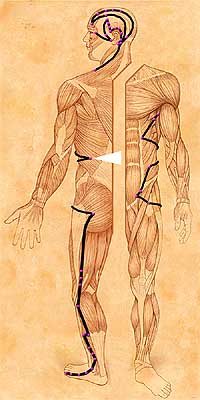

| GB25 • Jing Men • Gall Bladder 25 Capital Gate. Front Mu Point of the Kidneys that connects with Back Shu BL23. | ||||||||

| Location: On the lateral abdomen at the lower border of the free end of the twelfth rib. | ||||||||

| Abdominal Distention • Back Pain • Borborygmus • Diarrhea • Failure Of The Water Passages To Flow • Lateral Costal Region • | ||||||||